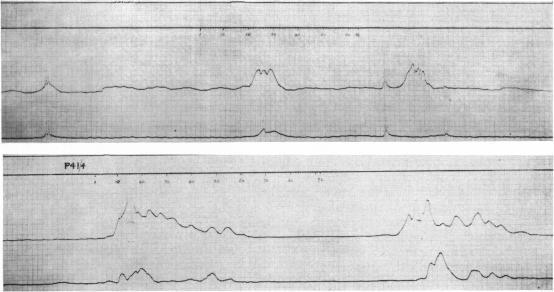

THE INTRALUMINAL PRESSURE PATTERNS IN DIVERTICULOSIS OF THE COLON.3. THE EFFECT OF PROSTIGMINE. IV. THE EFFECT OF PETHIDINE AND PROBANTHINE.

Gut. 1964 Aug;5(4):365-73. doi: 10.1136/gut.5.4.365.